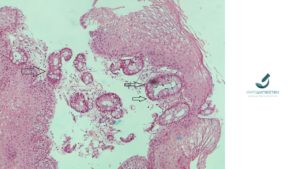

Ο οισοφάγος Barrett είναι η μετατροπή της επιφάνειας του τοιχώματος του οισοφάγου (ο βλεννογόνος του) σε επιφάνεια που μοιάζει με αυτή του στομάχου (γαστρική μεταπλασία – πρόδρομες αλλοιώσεις Barrett). Επιπλέον υπάρχουν αλλοιώσεις των κυττάρων σε αυτές τις θέσεις, όπου εμφανίζονται τα “καλυκοειδή κύτταρα” (βλέπε βέλη στην φωτογραφία). Αυτά τα κύτταρα χαρακτηρίζουν πλέον την γαστρική μεταπλασία ώς εντερική μεταπλασία. Η τελευταία κατάσταση είναι η χαρακτηριστική αλλοίωση της πάθησης που ονομάζεται “οισοφάγος Barrett”.

Στην φωτογραφία απεικονίζεται τμήμα από το τοίχωμα του οισοφάγου (βιοψία). Τα βέλη αναδεικνύουν τα “καλυκοειδή κύτταρα”. Ο οισοφάγος Barrett διαγιγνώσκεται συνδυάζοντας τα ευρήματα του παθολογοανατόμου στο μικροσκόπιο (μετά τη λήψη της βιοψίας από τον γαστρεντερολόγο), με τα ευρήματα του γαστρεντερολόγου κατά την οισοφαγοσκόπηση. Η μικρή πιθανότητα που έχει αυτή η πάθηση να αναπτύξει δυσπλασία (βλέπε άρθρο “Οισοφάγος Barrett με δυσπλασία”), η οποία μπορεί να εξελιχθεί σε καρκίνο, θέτει την ανάγκη συστηματικής παρακολούθησης από τον γαστρεντερολόγο με την διενέργεια οισοφαγο-γαστροσκόπησης και την λήψη βιοψίας για σύγκριση της εικόνας με την αρχική εικόνα (που είχε τεθεί η διάγνωση αρχικά). Υπάρχουν περιπτώσεις που τα “καλυκοειδή” κύτταρα – η παρουσία των οποίων θα καθορίσει την διάγνωση- δεν είναι εύκολα ορατά κατά την παρατήρηση στο μικροσκόπιο. Τότε ο παθολογοανατόμος έχει στην διάθεσή του ειδικότερες τεχνικές (ιστοχημικές χρώσεις – Alsian Blue – PAS διαστάση) που μπορεί να χρησιμοποιήσει στο υλικό που εξετάζει και οι οποίες θα τον βοηθήσουν να αποκαλύψει αυτά τα κύτταρα.